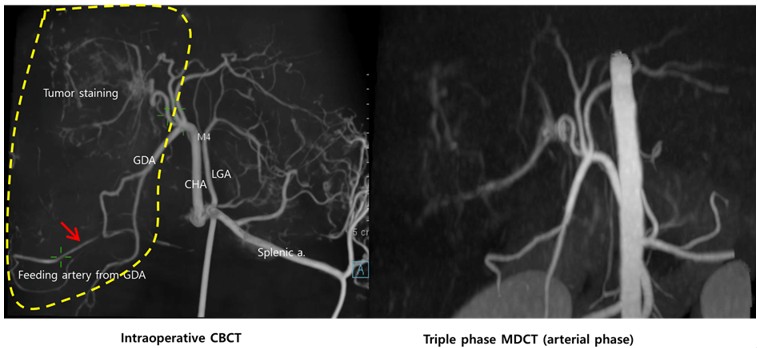

전성훈 센터장은 발표에서 “3차원 혈관조영술을 이용할 경우 간암으로 공급되는 영양동맥을 보다 정확하게 파악할 수 있고, 간 내에 위치하는 영양동맥뿐만 아니라 간 외에서 공급되는 영양동맥(collateral/extraphepatic feeding artery)까지 직접 확인할 수 있어 더 세밀하고 정확한 치료가 가능하다”고 설명했다.

특히 이번 회고 분석에 포함된 18마리 환자 중 7마리에서는 간 외에서 공급되는 영양동맥이 확인됐으며, 그중 3마리는 기존 CT 영상에서 확인되지 않았던 혈관이 3차원 영상으로 파악되어 추가 치료가 이루어졌다. 이를 통해 색전술의 효과는 더 증대되고, 다른 정상적인 혈관으로 색전 물질이 새어나가 발생할 수 있는 비특이적 색전 부작용(non-target embolization)도 최소화했다.